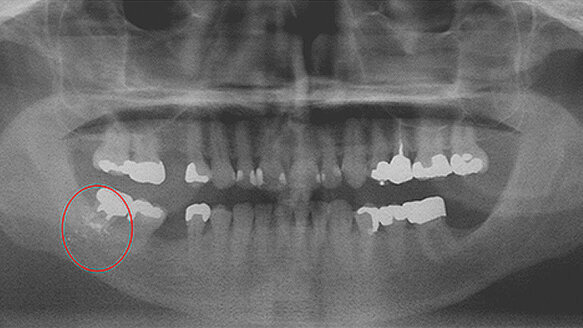

Comprehensive oral and maxillofacial examination included an intraoral and extraoral exam, full-mouth periapical X-rays and a panoramic radiograph. Among other clinical findings, the panoramic radiographs revealed incidental foreign bodies, most likely amalgam, embedded in the soft and/or hard tissue of the oral cavity due to iatrogenic treatment (Fig. 1).

While the flaps were reflected, an alloy core buildup was performed. The foreign bodies visible in the radiographic images are most likely amalgam alloy particles that either became trapped in the apical portion of the flap or in the interstitial tissue.